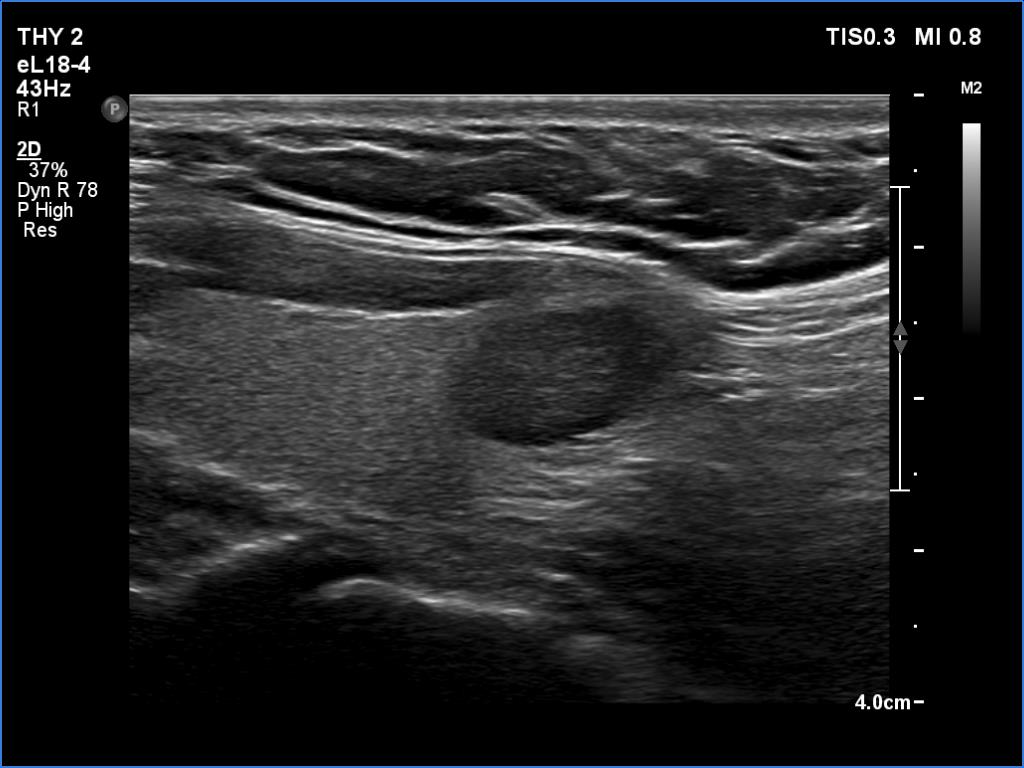

Ultrasonography. The thyroid was echonormal. There was a moderately hypoechoic lesion in the lower pole of the right lobe. The lesion presented no suspicious findings.